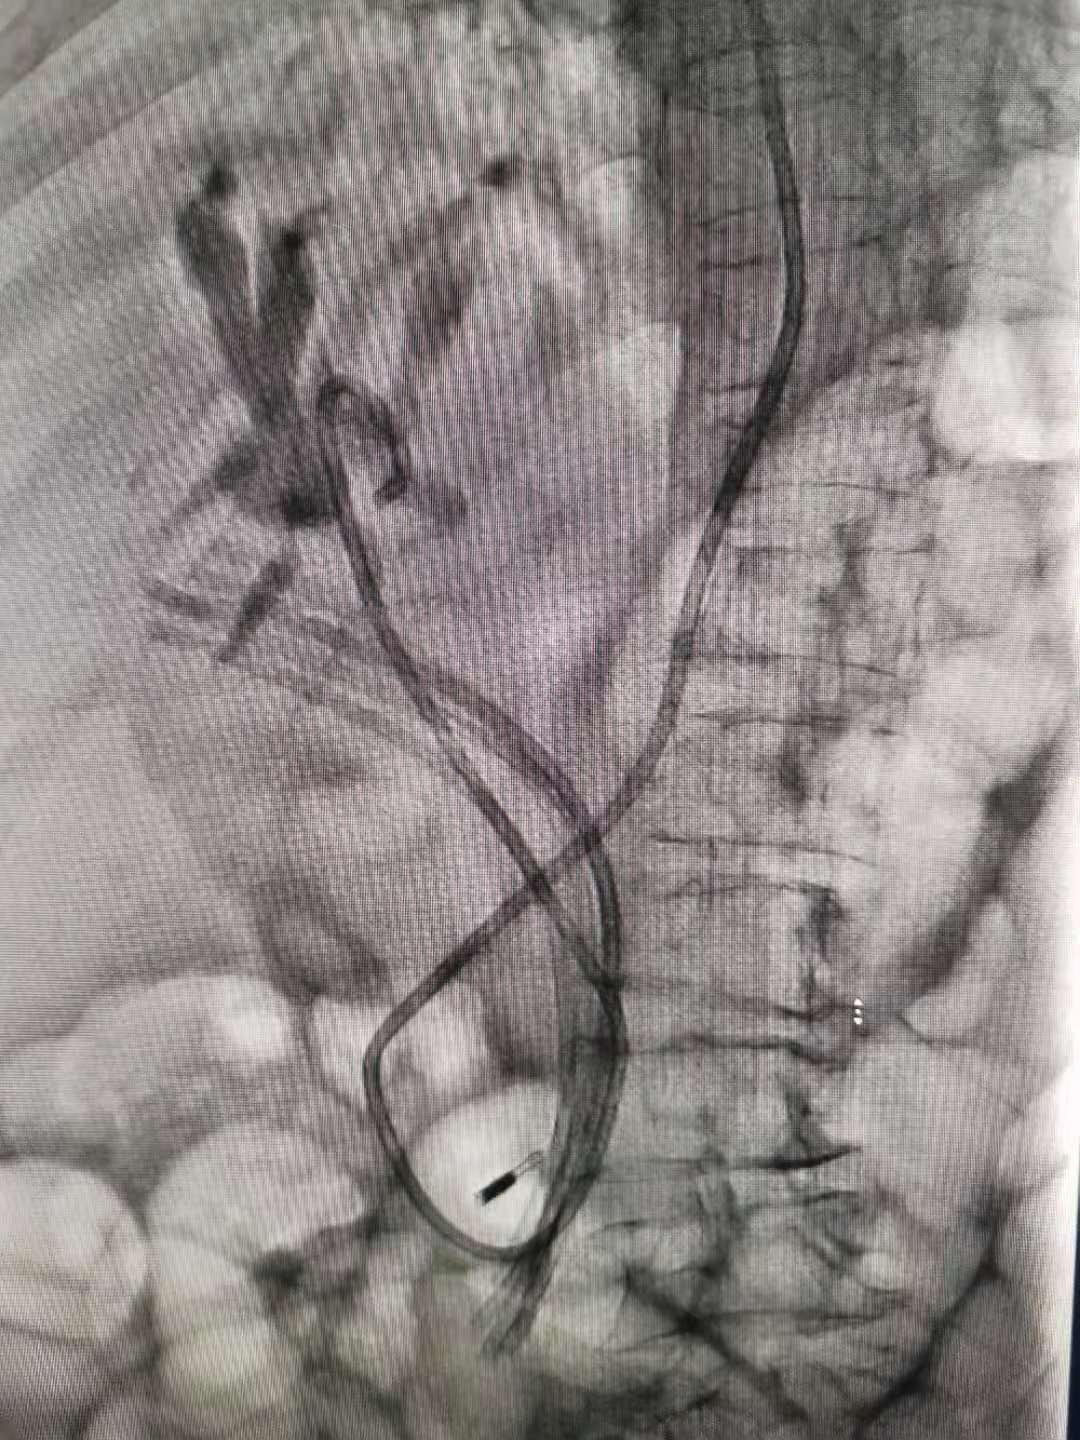

胆胰管开口在十二指肠降部,ERCP操作需将十二指肠镜从口腔插入患者体内,经食管、胃部至十二指肠降部、经十二指肠乳头注入造影剂,由于镜身盘绕及视线局限,很难前进,可谓每一毫米都需要调整定位,非常考验操作者的技术。经过反复探查找到李奶奶的嵌顿于胆总管内的(异物)塑料支架,章诺贝教授迅速插入取石网篮将其安全取出,同时见数枚大小不等的结石随之掉入十二指肠腔内,而结石最大者足有10毫米。术中并留置5根塑料支架于肝总管,为避免支架滑脱置入一枚和谐夹于乳头表面进行塑形,最后置入一根鼻胆道引流管于左肝管,胆汁引流通畅,全操作过程一气呵成,耗时五十分钟!